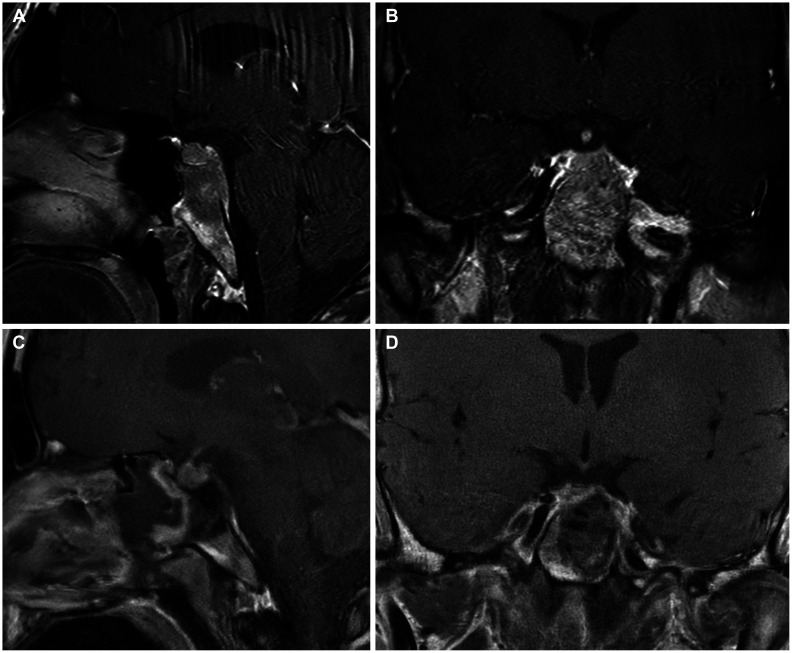

Giant cell tumors (GCTs) are locally aggressive primary bone tumors of osteoclast-like cells. Most GCTs occur within the long bones, and primary GCTs involving the clivus are extremely rare. We present the case of an 18-year-old boy with binocular horizontal diplopia with an insidious onset who was found to have a hypointense enhancing mass involving the clivus and left side dorsum sellae on magnetic resonance images. The tumor was completely resected via an endoscopic endonasal transclival approach, and histopathologic examination via immunohistochemistry indicated a GCT. The patient's left abducens nerve palsy improved slightly after surgery. Because of the rarity of GCTs, there is no consensus about the definitive treatment protocol. However, we suggest that gross total resection is the treatment of choice, and denosumab plays a critical role in patients with subtotal resection.